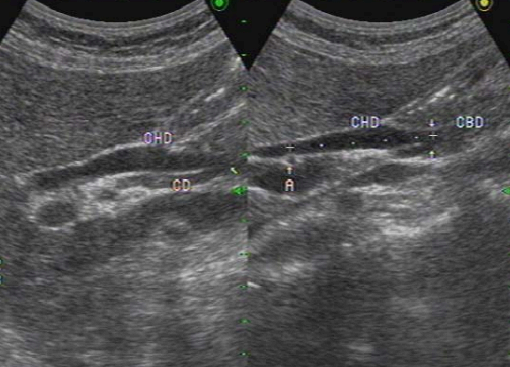

총담관(CBD) 확장 시 간동맥 (hepatic artery) 이 보이는 단면에서 wall 은 제외하고 측정한다. 총담관을 측정할 때 간동맥은 랜드마크가 된다.

- 총담관(common bile duct)의 직경은 7mm를 초과하지 않는다 (예외: 고령자, cholecystectomy 인경우 7~11mm 정상으로 간주한다.)

- 총 간관(common hepatic duct)은 4mm보다 작다.

- 간외담관(extrahepatic bile duct)은 총 간관(CHD)과 총담관(CBD)으로 나뉘고 그 끝은 십이지장 내 유두부이다.

extrahepatic bile duct 3) 지방식 (fatty meal)